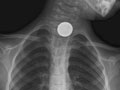

A chest X-ray is a picture of the chest that shows your heart, lungs, airway, blood vessels, and lymph nodes. A chest X-ray also shows the bones of your spine and chest, including your breastbone, your ribs, your collarbone, and the upper part of your spine.

A chest X-ray can help find some problems with the organs and structures inside the chest. Usually two pictures are taken, one from the back of the chest and another from the side. In an emergency when only one X-ray picture is taken, a front view is usually done. Doctors may not always get the information they need from a chest X-ray to find the cause of a problem. If the results from a chest X-ray are not normal or do not give enough information about the chest problem, more specific X-rays or other tests may be done, such as a computed tomography (CT) scan, an ultrasound, an echocardiogram, or an MRI scan.

- Find foreign objects, such as coins or other small pieces of metal, in the tube to the stomach (esophagus), the airway, or the lungs. A chest X-ray may not be able to see food, nuts, or wood fibers.

- A foreign object is seen in the esophagus, breathing tubes, or lungs.